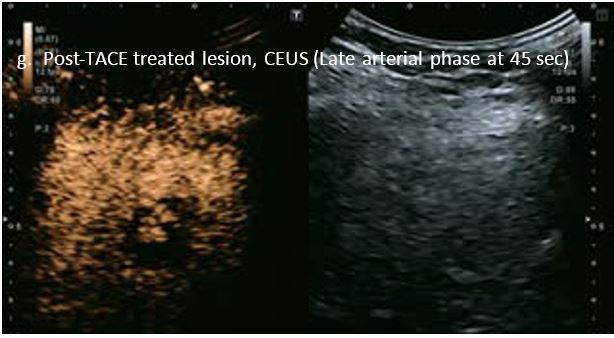

Оцінка результатів лікування ГЦК

Проведено повторне обстеження 79-річного чоловіка з цирозом печінки В, ускладненим ГЦК, після транс-артеріальної хіміоемболізації (ТАХЕ). Було виявлено нове ураження, розташоване поруч з ураженням після ТАХЕ. На сірошкальному зображенні чітко видно нове ураження, але складно виявити рецидив ГЦК в зоні ураження після ТАХЕ. За допомогою кольорового картування SMI (cSMI) можна побачити розвинену судинну мережу всередині нового вогнища ураження. Для оцінки результату лікування було виконано CEUS. За допомогою CEUS можна легко дослідити як нове ураження, так і рецидив ГЦК у вогнищі ураження після TACE. Нове ураження демонструє гіперпосилення артеріальної фази і відсутність вимивання до 5 хвилин, отже, це ураження LI-RADS 4, ймовірна ГЦК за критеріями LI-RADS. Підживлюючі судини можна чітко спостерігати в ранній артеріальній фазі. Для ураження після TACE, більша його частина не підсилюється, однак, в артеріальній фазі спостерігається ділянка гіперпосилення у верхній частині лікованого ураження, що вказує на рецидив ГЦК.

Малюнок 10